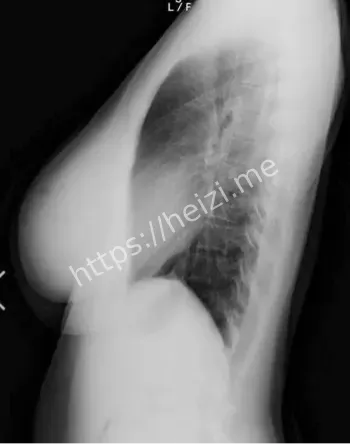

哎呀,这天木纯的八卦又炸锅了,最近网上疯传她的X光照片,说是巨乳假体曝光,粉丝们一看都傻眼了。这位1995年生的小纯,本来就是以童颜巨乳出名的AV女优,身高才148公分,三围99I-57-84,那对G杯胸器大得像漫画里蹦出来的,二次元天乳的称号不是白叫的。报道说X光片显示胸部结构不自然,有人直呼卧槽太夸张了,怀疑是假体植入啥的。话说回来,这事儿一出,黑子网用户们就热闹了,各种分析帖刷屏,说这不光是身材秘密,还牵扯到AV圈的整形风潮。

啧啧,天木纯的二次元天乳这回可出大事儿了,X光照片流出后,身材秘密被扒得底朝天。网传她那99公分的胸围太不科学了,童颜小身板配巨乳,粉丝们以前直呼福利,现在却开始纠结假体问题。报道分析说,X光显示植入物痕迹明显,可能是硅胶假体啥的,这在AV女优圈挺常见,追求完美身材嘛。可天木纯本人没回应,粉丝热议分成两派,一派说天生丽质,一派说整形无罪。哎,这身材秘密一曝光,二次元天乳的魅力打折了?大家说,这事儿提醒女优们,真实比假象重要,粉丝也得学会欣赏内在。

哈哈,这天木纯巨乳假体争议可真叫人看热闹不嫌事儿大,X光曝光后,粉丝热议焦点全在她身上了。AV女优圈里,她以童颜巨乳闻名,二次元天乳粉丝无数,可这回X光片一出,直指假体植入,网友们炸了锅,有人说卧槽确实好大太假了,有人辩护说天生就这样。报道说,事件源于某论坛泄露的照片,专业人士分析胸部密度异常,疑似假体手术痕迹。这粉丝热议不光是八卦,还涉及对女优形象的认知,大家说AV界整形常态,但曝光后就尴尬了,得保护隐私啊。

哇塞,天木纯X光照片流出这事儿,社会影响可不小,AV女优圈的假体风波又被推上风口。报道说,这照片疑似医疗记录泄露,巨乳结构一览无余,二次元天乳的完美形象瞬间崩塌,粉丝们从惊呼福利到热议争议。童颜巨乳是她的卖点,可假体曝光后,大家开始讨论AV产业的身材压力,女优们为工作整形在所不惜,这社会影响深远啊。话说,这事件还牵扯隐私权,X光本是私密,怎么就流出了?得加强保护,不然谁敢安心工作。